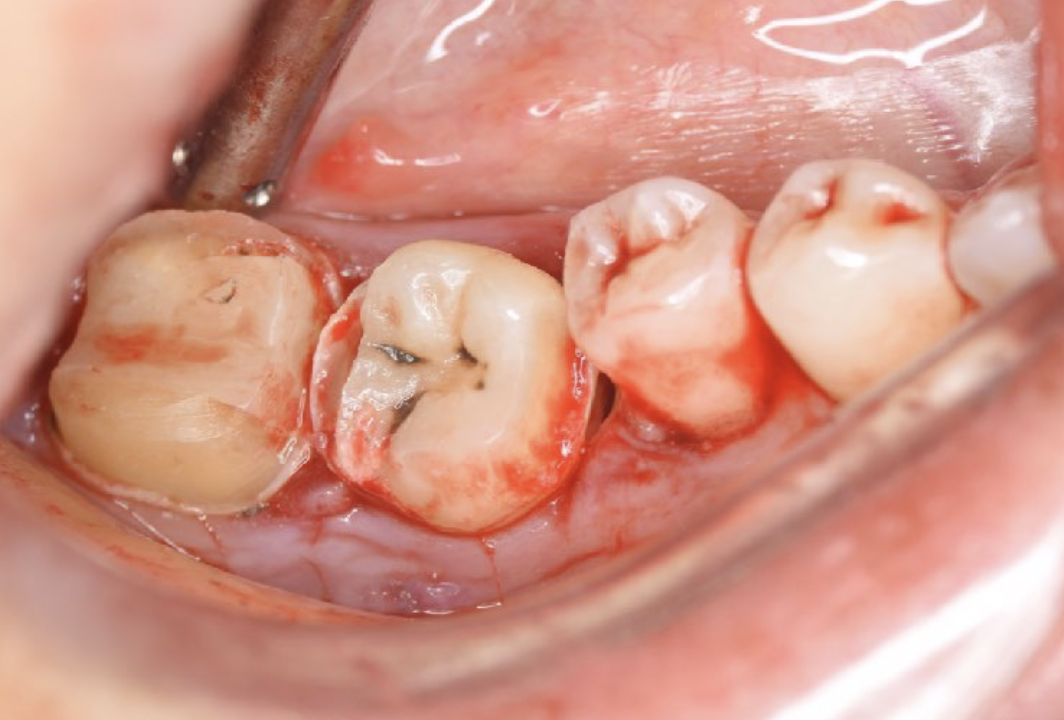

A 27-year-old female patient came to us with discomfort in the right lower jaw (Figure 1). Her primary symptoms were pain in the lower right tooth when biting and discomfort associated with not being able to chew well with the lower left single denture. The patient was married and had one young child, and previously received dental treatment in China, then had returned to Japan for childbirth and early childcare. The patient was a nonsmoker with moderate plaque control and medical history taking revealed no problems. In clinical and radiographic examinations, a root fracture was observed on tooth #46, which had been endodontic ally treated and restored with a full-cast metal crown. Periodontal probing revealed a pocket depth of 8 mm on the buccal center side of the tooth. No pain was detected with percussion and mobility of the tooth was normal. (Figure 1, Figure 2, Figure 3).

Figure 2.Pre-treatment X-ray findings. A cystic lesion was found in the mesial and distal roots apex, and root nodule of #46.

Figure 3.Preoperative intraoral findings. A metal crown was inserted at #46 and bleeding on probing during the periodontal pocket examination was noted.